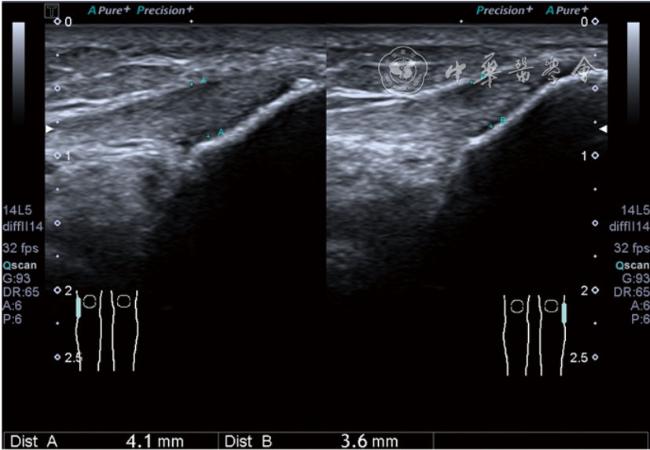

4.神经卡压液压松解加药物注射治疗。膝关节神经卡压主要涉及膝内上支、膝外上支、膝内下支、髌下支。可根据神经支配区域的临床检查确定卡压神经。临床上隐神经髌下支卡压常见。隐神经髌下支从隐神经发出后穿缝匠肌至膝内前下方,与深筋膜紧密相连(图24)。隐神经髌下支卡压出现膝关节内下侧酸痛、麻木,胫骨内侧髁压痛阳性,Tinel征阳性,局部皮肤痛觉减退。确定诊断后可行隐神经髌下支液压松解。患者平卧位,膝关节屈曲30°,下面垫一软枕。一般选用10 MHz以上超声探头,穿刺区域常规消毒,探头涂抹耦合剂后套入无菌手套碘伏消毒或使用无菌耦合剂。首先扫查神经短轴切面,确定神经后旋转为长轴切面引导注射。选用25G穿刺针头,抽吸0.5%利多卡因4 ml+地塞米松3 mg,从近端穿刺,沿神经表面纵轴方向,确定针尖在神经膜外后推注药物进行松解,注射完毕后拔出针头(图25),局部压迫2分钟,创可贴覆盖。

图25 超声引导下隐神经髌下支卡压液压松解加药物注射治疗